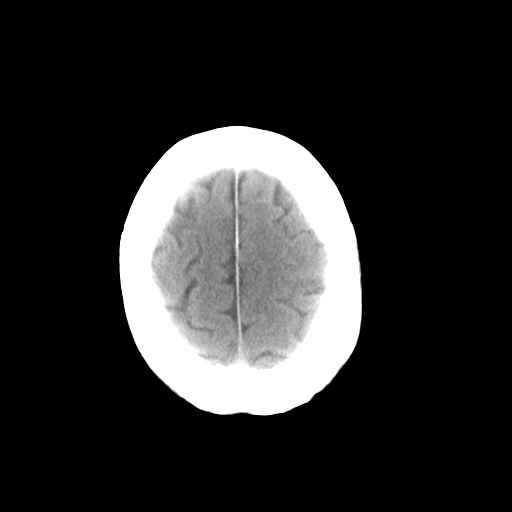

以下是引用影像孺子牛在2008-11-11 23:11:00的发言:[br]还是做个mri吧,无必要复查ct。